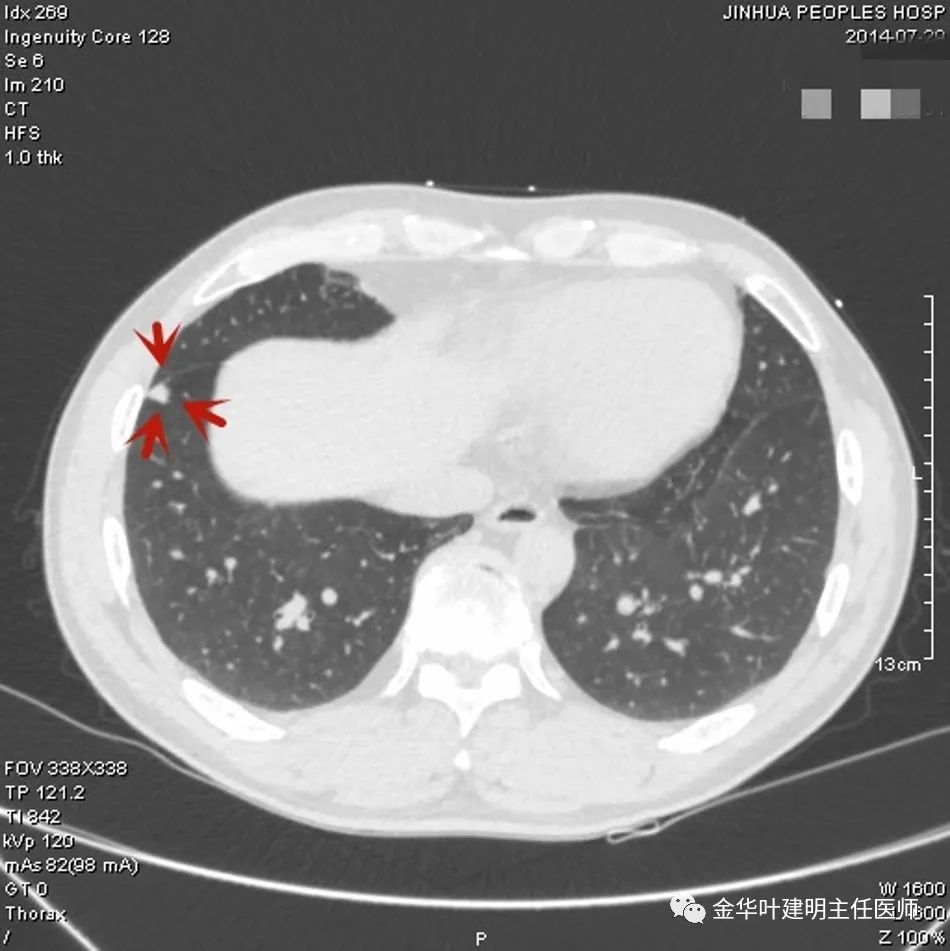

上图是结核,但这么明显的左上肺占位,谁又能从影像上排除它是肺癌呢?当然回头看,病灶中间密度低(可能液性)、周围一圈强化明显些、与纵隔组织关系密切但没有明显侵犯,界限仍然清楚,是有良性可能的。